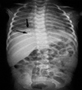

Fractura de la parte posterior de las costillas

Son estas lesiones poco frecuentes en el niño por caídas banales; únicamente se producen si estos han sido víctima de un accidente de tránsito o por abuso. Pueden verse en los niños pequeños, menores de 3 años en el Síndrome del niño sacudido al sujetarlos por el tórax fuertemente tanto en sentido antero-posterior o lateral. En el caso del niño golpeado, se produce como vemos en esta diapositiva, fracturas en la parte posterior de las mismas. La vemos con más frecuencia entre T-4 y T-9 a nivel de la línea axilar, arco posterior y postero-lateral no siendo infrecuente la disyunción condrocostal. Las hacen muy sospechosas cuando se combinan con fracturas de los huesos largos, siendo su mecanismo de producción al ser pateados o golpeados por la parte posterior del tórax o parándose sobre este. Viejas fracturas de costilla pueden semejar radiológicamente un tumor por las lesiones bulosas o líticas que pueden verse en estos casos.